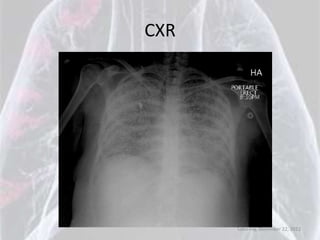

CXR

Saturday, December 22, 2012